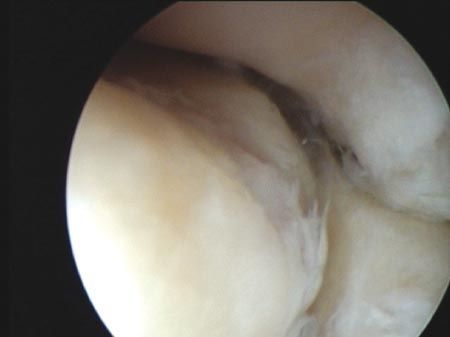

Technique Arthrolyse arthroscopique du coude - Intérêts et limites , Jérôme Pierrart Hôpital Avicenne, Assistance Publique-Hôpitaux de Paris, Université Paris 13, Sorbonne Paris Cité, Bobigny, France , Christian Dumontier Hôpital Saint-Antoine, Paris, France N°229 - Décembre 2013 ● 24 min de lecture

Technique Traitement arthroscopique de l'épicondylite latérale (tennis elbow) , Christian Dumontier Hôpital Saint-Antoine, Paris, France , V. Beauthier Hôpital saint Antoine - 75012 Paris N°197 - Octobre 2010 ● 25 min de lecture